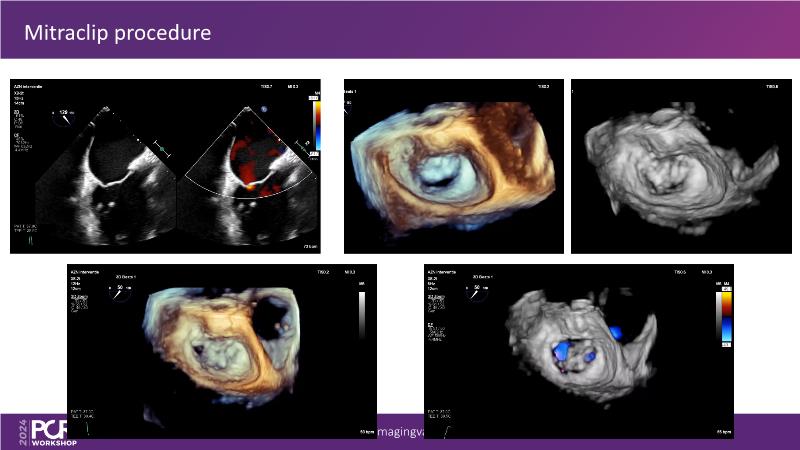

Explore cutting-edge transcatheter valve interventions for mitral and aortic valve disorders, including valve-in-valve procedures and management strategies for paravalvular leakages, and learn about diagnosing and treating mitral annular calcification and transcatheter options in infective endocarditis.

- To get tips and tricks for guidance of transcatheter intervention